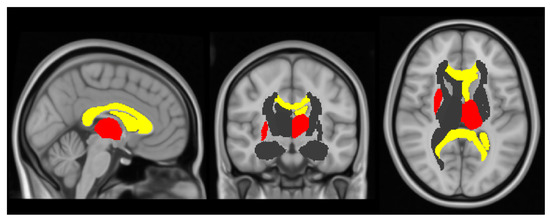

- Patenaude, B.; Smith, S.M.; Kennedy, D.; Jenkinson, M. A Bayesian model of shape and appearance for subcortical brain segmentation. Neuroimage 2011, 56, 907–922. [Google Scholar] [CrossRef] [PubMed]

| Left ventricle, mm3 | 9375.4 (5855.4) | 6818.0 (4564.0) | −2949.8 (−923.9, −4975.7) * |

| Left thalamus, mm3 | 7714.1 (940.8) | 8343.1 (922.0) | 701.9 (1019.6, 384.3) ** |

| Right putamen, mm3 | 5030.2 (628.2) | 5254.4 (560.5) | 239.9 (443.6, 36.3) |

| FA corpus callosum | 0.6 (0.1) | 0.7 (0.0) | −0.0176 (−0.0349, −0.0002) |